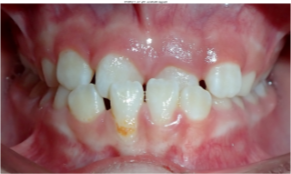

| Underbite | The top front teeth are behind the bottom front teeth when you bite | ![]() | Limited braces or a retainer to move the front teeth and/or a headgear to help the upper jaw grow |